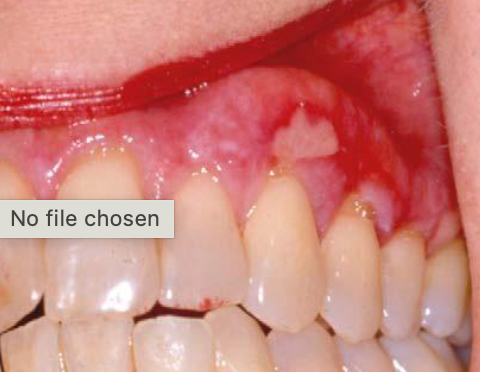

erosive lichen planus

immune mediated disease causing ulcerations and erythema, PAINFUL

most common locations for EROSIVE LICHEN PLANUS